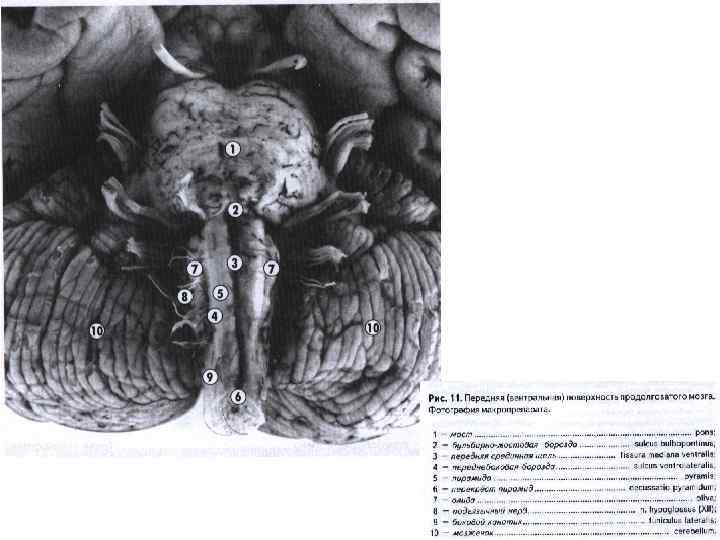

Ствол мозга с вентральной стороны): III — глазодвигательный нерв; IV — блоковый нерв; V — тройничный нерв; VI — отводящий нерв; VII — лицевой нерв; VIII — предверно-улитковый нерв (слуховой); IX — языкоглоточный нерв; X — блуждающий нерв; XI — добавочный нерв; XII — подъязычный нерв; 1 — ножка мозга (средний мозг); 2 — перекрест пирамид (верхний шейный отдел спинного мозга); 3 — боковой канатик; 4 — передняя боковая борозда; 5 — олива; 6 — пирамида продолговатого мозга; 7 — мост